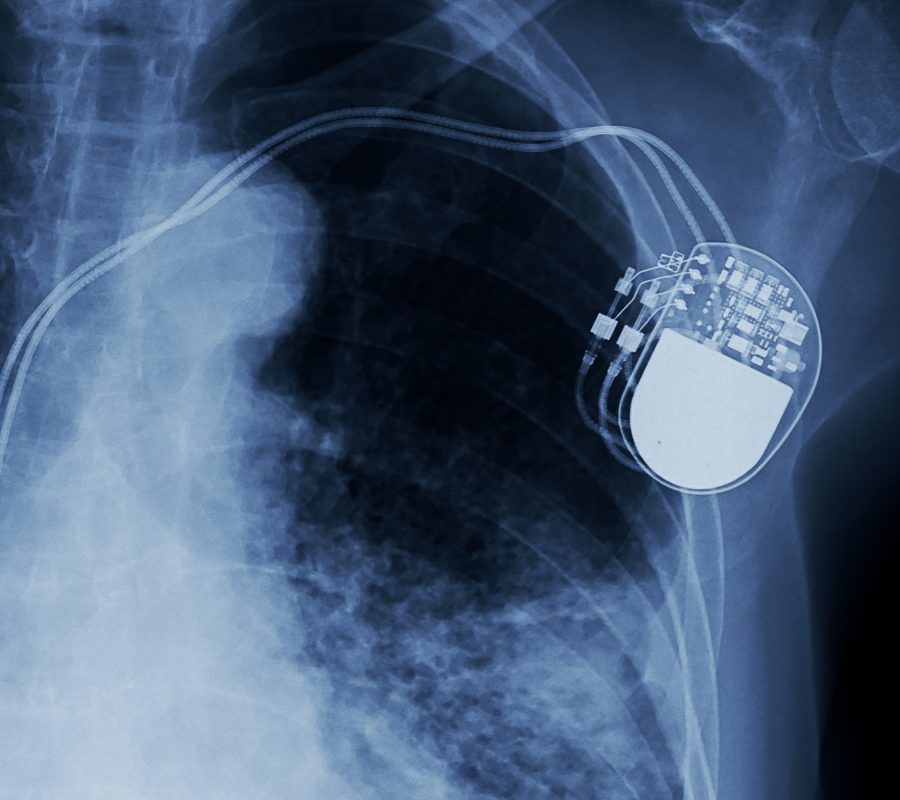

Medical device and diagnostics companies have taken great strides in the development of newer technologies to provide better patient assessment and treatments. Devices of the future will require smaller features, lighter materials, and improved stability. Not only is it important to assess the materials and chemistry in medical devices, but it is also equally as important to assess medical device electronics to ensure safety and reliability. From hearing aids to heart pacemakers to catheters and more, advanced electronics can be seen in many of today’s medical devices.

Every day the medical industry lunges forward with more advanced instruments and higher quality consumer products. This new level of sophistication also translates into more complex R&D processes. As the manufacturing process gets more complex, there are many more opportunities for things to go awry. Identifying, diagnosing, and remedying failures becomes dramatically more challenging. Our experienced engineers and scientists possess a comprehensive array of advanced tools and techniques that can perform failure analysis on a large range of electronic devices.

Eurofins EAG Laboratories offers the most diverse and comprehensive suite of testing and engineering support available for medical devices. With failure analysis services that range from non-destructive examination to physical analysis for root cause identification, our failure analysis team has the engineering expertise to help solve problems at any phase of the product cycle. EAG understands the stringent regulations, requirements and expectations of medical devices and are therefore the perfect partners to assist with advancements in the medical device industry.